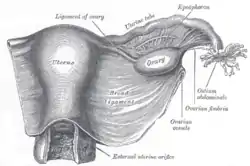

Support

The uterus is primarily supported by the pelvic diaphragm, perineal body, and urogenital diaphragm. Secondarily, it is supported by ligaments, including the peritoneal ligament and the broad ligament of uterus.[14]

Major ligaments

It is held in place by several peritoneal ligaments, of which the following are the most important (there are two of each):

| Name | From | To |

|---|---|---|

| Uterosacral ligaments | Posterior cervix | Anterior face of sacrum |

| Cardinal ligaments | Side of the cervix | Ischial spines |

| Pubocervical ligaments[14] | Side of the cervix | Pubic symphysis |

Blood supply

The uterus is supplied by arterial blood both from the uterine artery and the ovarian artery. Another anastomotic branch may also supply the uterus from anastomosis of these two arteries.